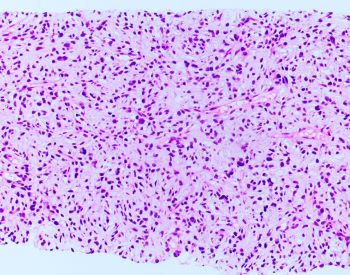

55 YOM presented with thigh mass. A biopsy was performed and showed the following lesion illustrated in the images. FISH analysis using a dual-color MDM2/CEN12 probe [Red=MDM2; Green=CEN12] was performed.

Histologically, dedifferentiated areas can be of high or low grade including area that resembles undifferentiated pleomorphic sarcoma, with pleomorphic spindle, polygonal, and multinucleated cells or with marked inflammation, or an area resembling inflammatory myofibroblastic tumor. Occasionally, the dedifferentiated component may resemble myxoid soft tissue neoplasm exhibiting myxoid stroma and delicate fibrovascular network entering the differential diagnosis with myxoid liposarcoma, myxofibrosarcoma, and low-grade fibromyxoid sarcoma. If present, the well-differentiated (lipogenic) component in dedifferentiated liposarcoma is mostly discrete showing an abrupt transition from the dedifferentiation component, but the two components can be intermingled in a mosaic pattern. Nonetheless, in small biopsies, only one component may predominate.